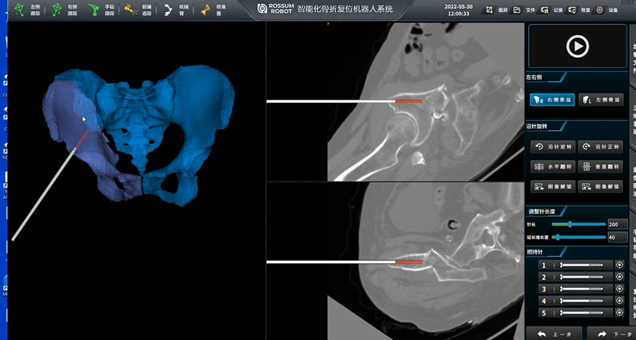

蒋协远:这方面有一系列的例子。以我们团队研发的“肩关节置换机器人”为例,它能很好地说明医工结合如何直接造福患者。

随着我国步入老龄化社会,肩关节骨折(也就是“肱骨近端骨折”)发病率越来越高。这类骨折的传统复位方法是要完全切开,复位后用钢板螺钉固定。这样的手术很复杂,且耗时较长,术后长期预后欠佳。不少患者的肩关节功能活动受限影响比较大。

“肩关节置换机器人”,正是为了精准、安全地解决这一痛点而诞生。它本质上是一个“智能导航+稳定执行”的系统。

手术前,我们会为患者做受伤肩关节CT扫描,机器人系统会自动构建出肩关节的三维模型,并智能规划出精准、对软组织牵拉影响最小的肩关节基座和假体的放置路径方案。随后,通过机器人按照规划好的路径完成手术。

我们研发的这款“肩关节置换手术机器人”是国内首个该领域手术机器人产品,也是国际上第3个。

对患者而言,它使得手术风险降低,出血量减少,肩关节置换假体放置得更精准,术后肩关节功能活动明显改善。对医生而言,它降低了体力消耗和操作风险,使肩关节置换手术变得标准化、可重复。

上图:肩关节置换手术机器人

第一个项目是“肩关节置换手术机器人”。

由我与北京埃斯顿医疗科技有限公司合作开发,这是国内首个肩关节机器人。它能够通过绳驱动技术、自动图像分割、健侧镜像参考、关节活动度预测等多项技术来提升手术精准度,减少对医生经验的依赖,从而降低肩关节置换手术风险和并发症率。

目前,这个项目已经完成型式检验及创新器械申报,进入临床试验阶段。